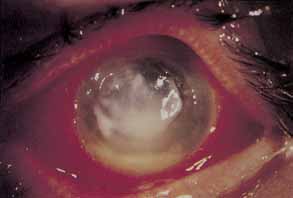

BACTERIAL KERATITIS

Infectious keratitis is the single most feared complication of contact lens wear.138 Corneal infections may range from small peripheral ulcers to large suppurative central ulcers. Infectious ulcers must be differentiated from sterile ulcers, particularly in association with disposable extended lens wear. Bacterial keratitis occurs most frequently in association with extended soft contact lens wear and least frequently among rigid PMMA wearers. Bacterial keratitis is by far the most frequent form of infectious keratitis associated with contact lens wear, with Pseudomonas aeruginosa being the most frequent isolate (Fig. 5). In most cases of infectious keratitis, there is an identifiable breach of contact lens care protocol that predisposes the patient to infection. It is imperative to make a swift and accurate diagnosis of infectious keratitis and to initiate appropriate topical antibiotic therapy to minimize visual loss secondary to stromal scarring.

Fig. 5 Central Pseudomonas keratitis with hypopyon.

The epidemiology of infectious keratitis associated with contact lens wear has been extensively examined over the past 15 years.20,139–158 A survey of ophthalmologists and households in New England produced estimates of the annual incidence of infectious keratitis associated with cosmetic extended (20.9 per 10,000 persons) and daily (4.1 per 10,000 persons) contact lens wear.139 The same study group estimated the annual incidence of infectious keratitis among aphakic contact lens wearers to be 52 per 10,000 persons and significantly higher for those who practiced extended wear.141 With estimates of 9 million daily lens wearers and 4 million extended lens wearers, this incidence translates to 12,000 new cases of infectious keratitis related to cosmetic soft contact lens wear annually in the United States alone.140,141 The relative risks of infectious keratitis with extended versus daily wear reveal that risk rises incrementally with the duration of extended wear.140 Advances in soft, silicone, hydrogel materials have reduced complications for extended wear, but the newer lenses have not been compared to older lenses in a large study of complication rates.22 Compared to daily contact lens wear, extended wear on a routine basis carries a 10 to 15 times increased risk of infectious keratitis.140 In addition, the risk for soft cosmetic daily wear exceeds that for daily rigid gas permeable lens wear.158 Daily disposable soft lens wear may afford the best strategy to avoid infection.31–33